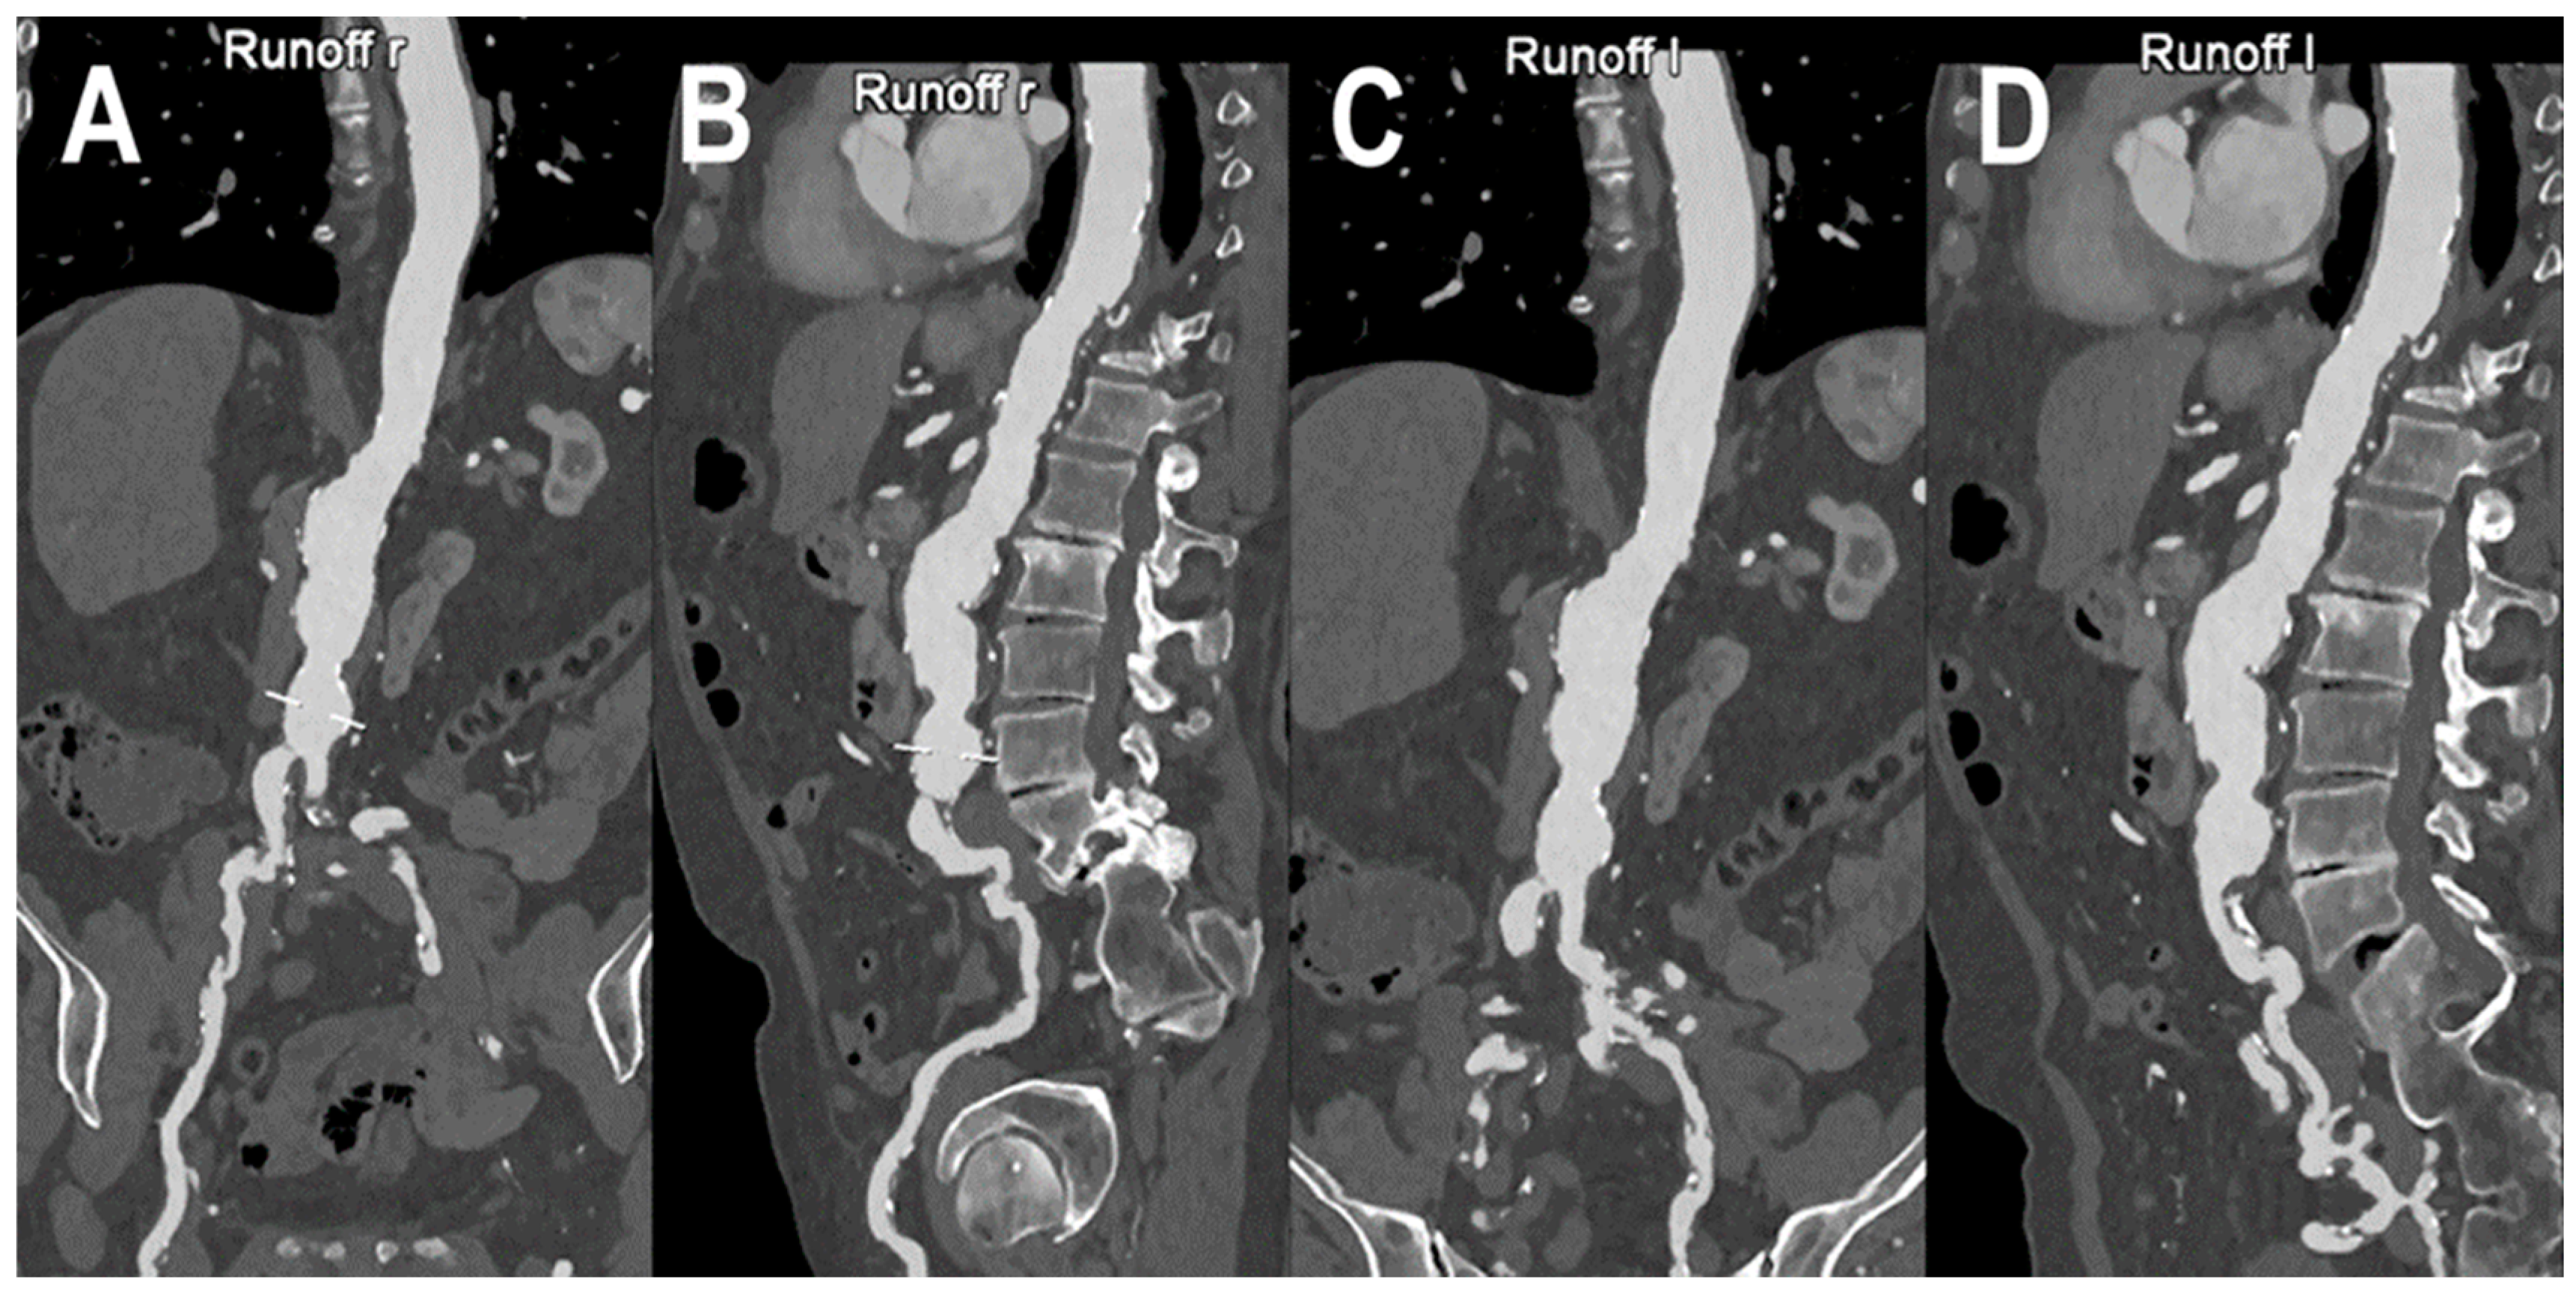

- Shwaiki, O.; Rashwan, B.; Fink, M.A.; Kirksey, L.; Gadani, S.; Karuppasamy, K.; Melzig, C.; Thompson, D.; D’Amico, G.; Rengier, F.; et al. Lower extremity CT angiography in peripheral arterial disease: From the established approach to evolving technical developments. Int. J. Cardiovasc. Imaging 2021, 37, 3101–3114. [Google Scholar] [CrossRef] [PubMed]

- Tanaka, R.; Yoshioka, K.; Takagi, H.; Schuijf, J.D.; Arakita, K. Novel developments in non-invasive imaging of peripheral arterial disease with CT: Experience with state-of-the-art, ultra-high-resolution CT and subtraction imaging. Clin. Radiol. 2019, 74, 51–58. [Google Scholar] [CrossRef]

- Leng, S.; Yu, Z.; Halaweish, A.; Kappler, S.; Hahn, K.; Henning, A.; Li, Z.; Lane, J.; Levin, D.L.; Jorgensen, S.; et al. Dose-efficient ultrahigh-resolution scan mode using a photon counting detector computed tomography system. J. Med. Imaging 2016, 3, 043504. [Google Scholar] [CrossRef]